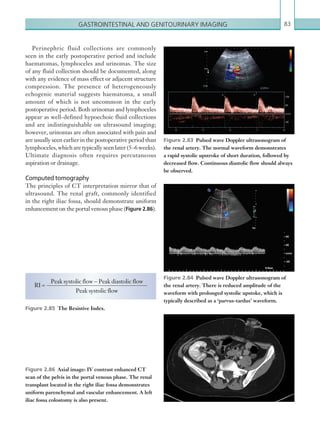

myeloproliferative disorders,

paroxysmal nocturnal

haemoglobinuria, Behçet’s

disease).